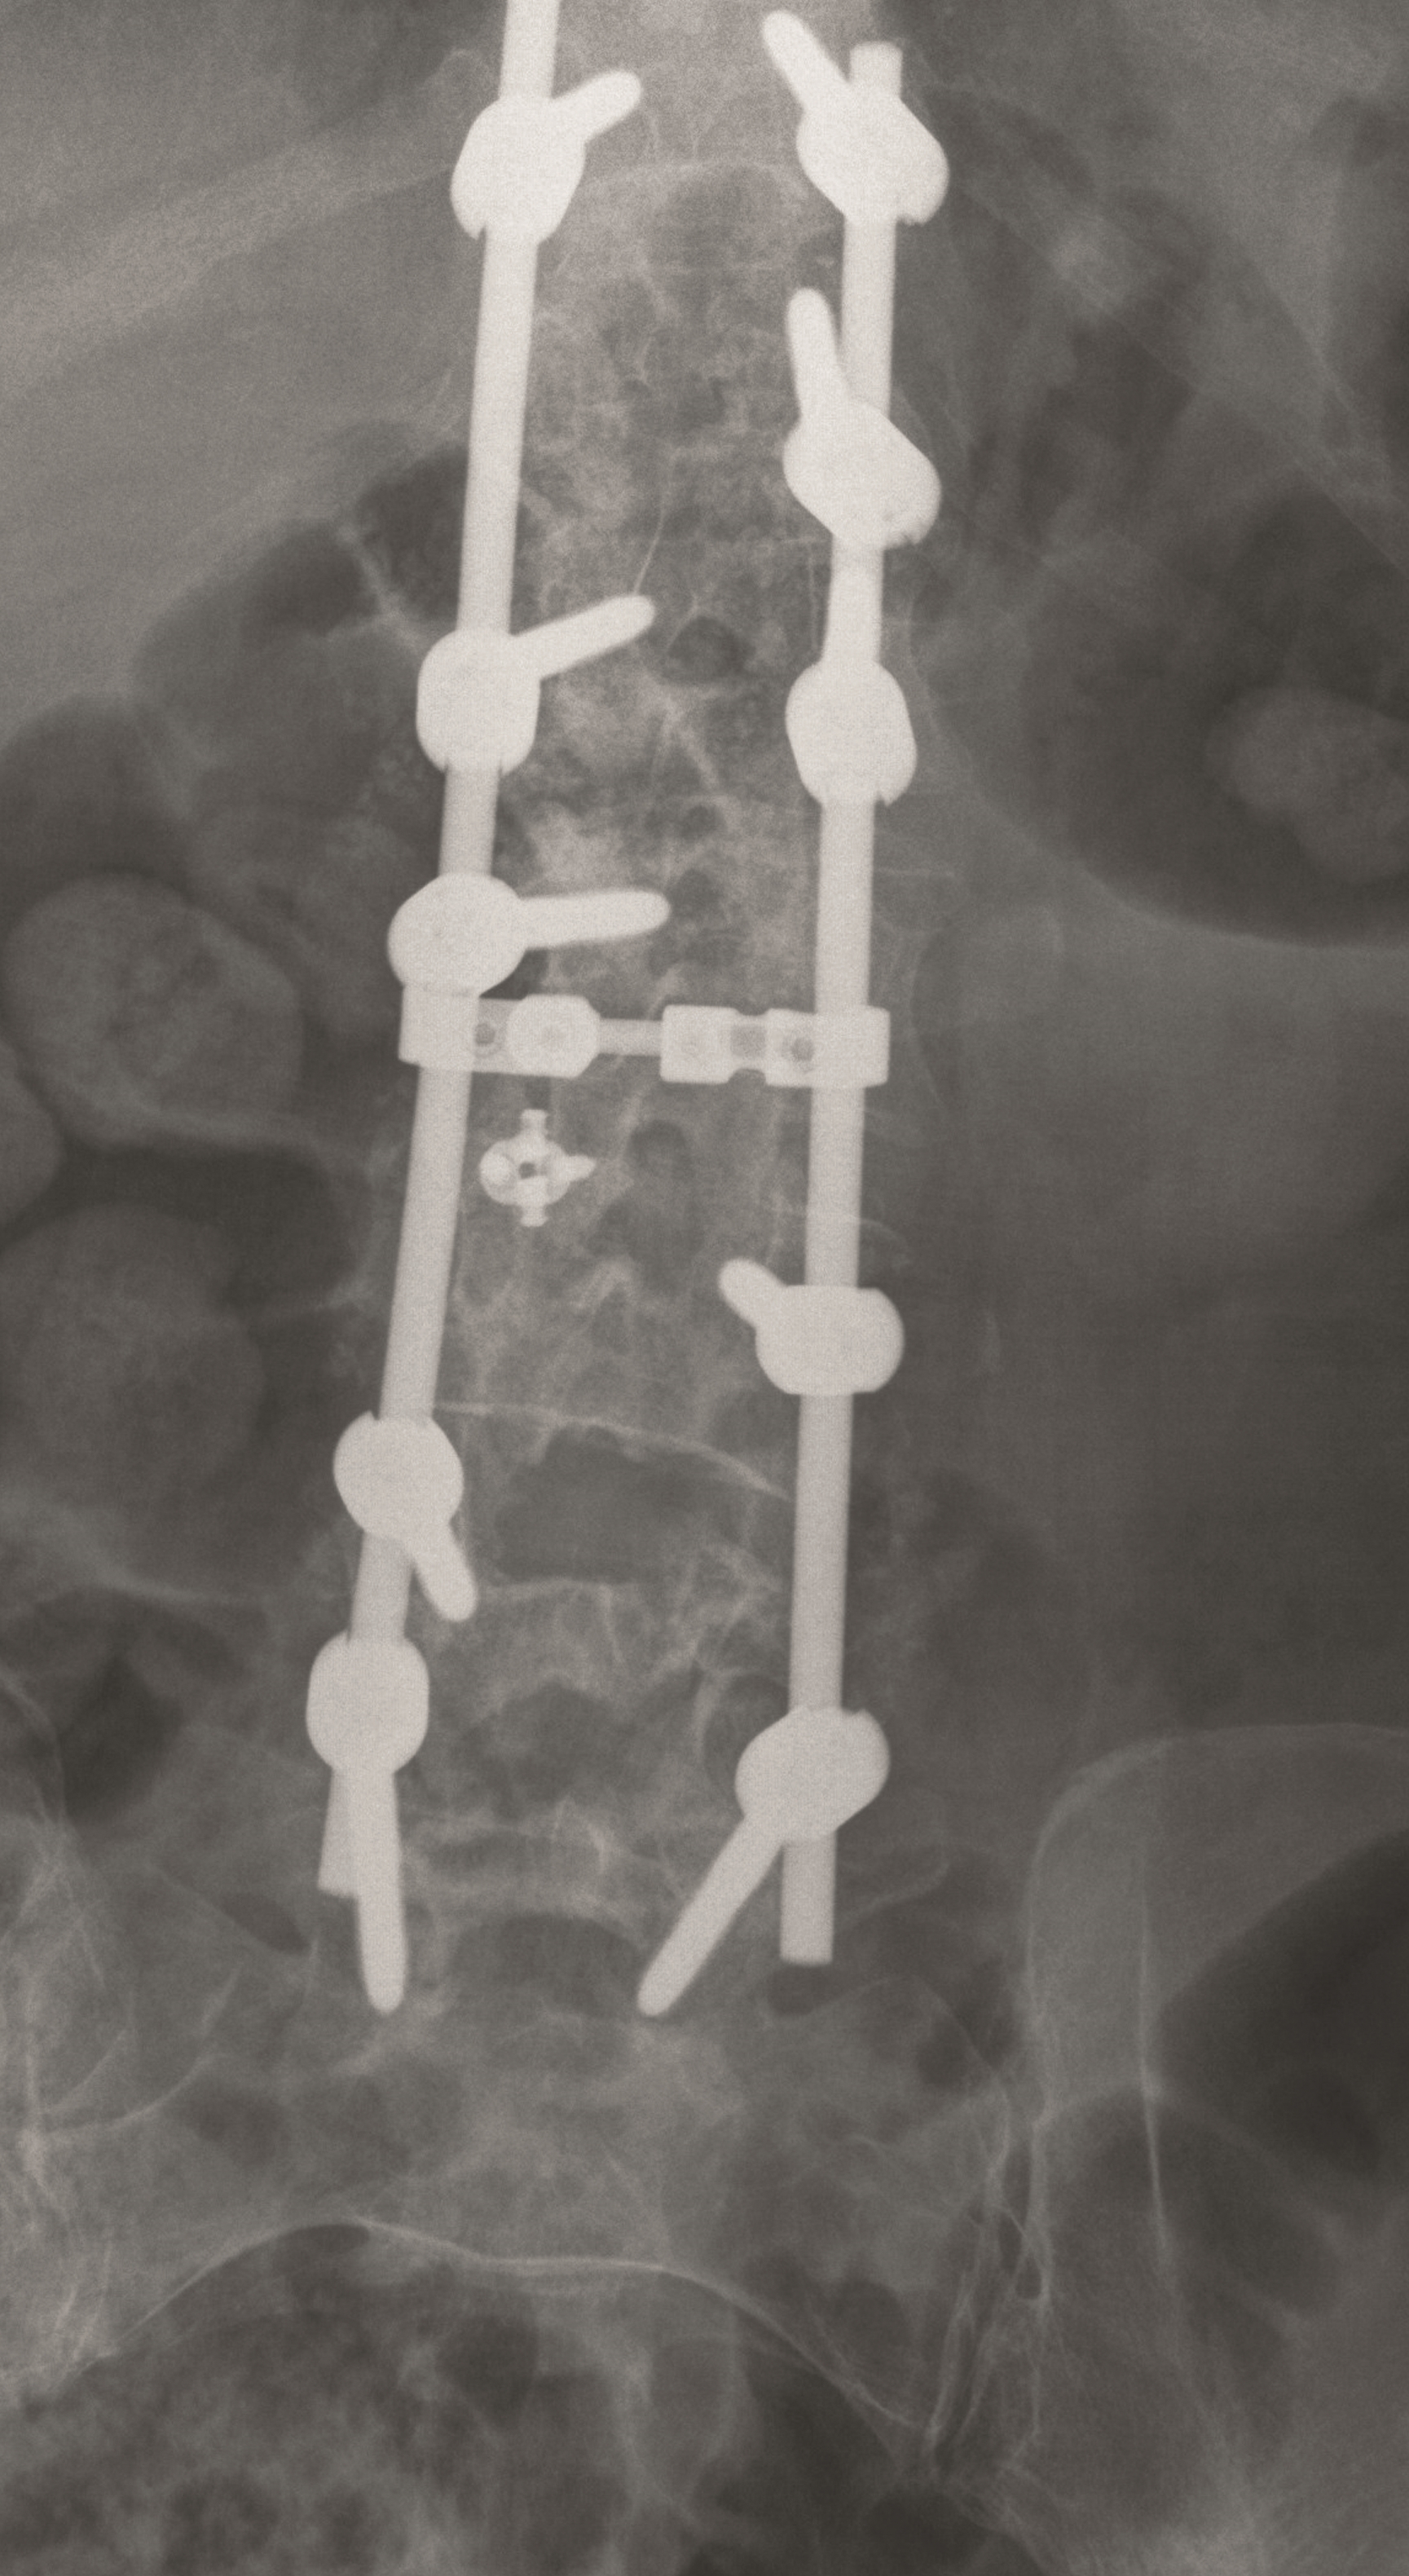

Case 5 : Degenerative scoliosis

A female patient 66-years-old with back pain, leg pain, and degenerative deformity. The x-rays show left convex degenerative scoliosis Cobb T12-L3 38. Nonoperative treatment failed. Treatment option was posterior fusion T11-L5, with URS Facet Wedge L2-L3 unilaterally.

A conventional approach for posterior correction was taken, with indirect Foraminal decompression and Facet Wedge fusion (apex curve). Facet Wedge introduction after curve correction with rod in situ. X-ray follow-up initially (Fig 20), with CT assessment of Facet Wedge fusion after 6 months (Fig 21).